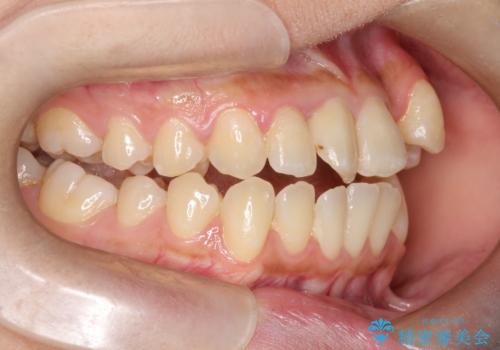

- 患者様は左上の八重歯を気にされて来院されました。八重歯による歯列の乱れだけでなく、翼状捻転(歯がねじれるように生えている状態)も見られました。目立たない矯正を希望されていたため、**インビザライン(マウスピース矯正)**を選択し、左上の小臼歯を抜歯してスペースを作りながら歯を並べる治療計画を立てました。しかし、治療の途中で翼状捻転の改善が十分に進まなかったため、患者様の希望も踏まえ、上顎のみワイヤー矯正に変更することとなりました。

治療開始時はインビザラインを使用し、全体の歯並びを整えながら抜歯スペースを活用して歯を後方へ移動させました。しかし、左上の八重歯のねじれが強く、マウスピースのみでは十分にコントロールできないことが判明。そこで、より細かく歯を動かすために上顎のみワイヤー矯正へ切り替えました。ワイヤー矯正によって翼状捻転も改善し、最終的にバランスの取れた歯並びと噛み合わせを実現。患者様からは「長い治療だったけれど、しっかり整って満足」と嬉しいお言葉をいただきました。